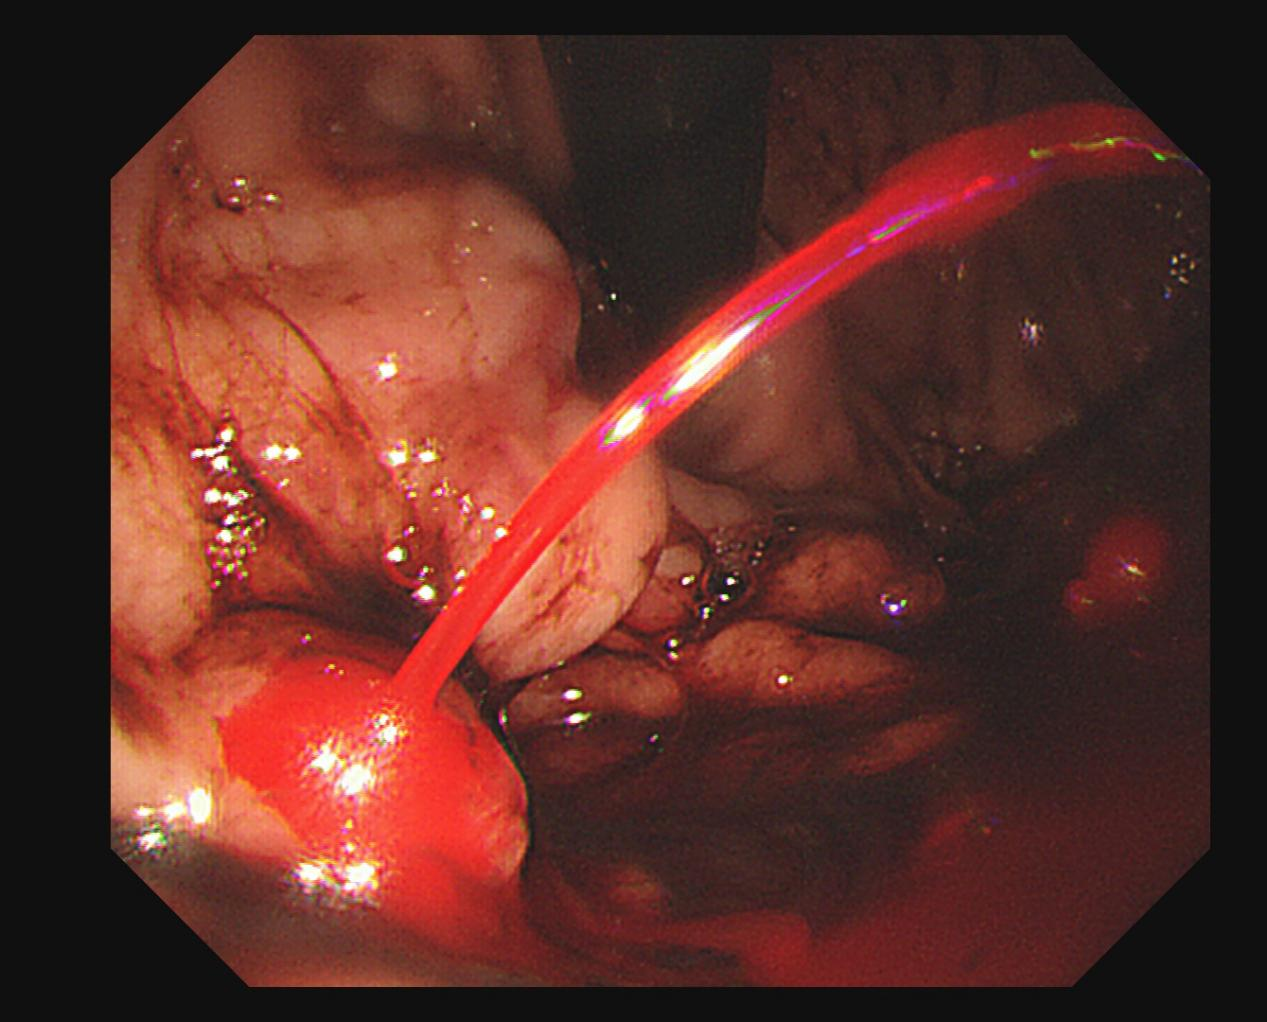

精准狙击:一场无声的镜下“止血战”

刘奎主任操作内镜注射针,精准刺入出血点旁的曲张静脉内。“推注组织胶!”特制的医用组织胶水被快速迅速注入血液。胶水遇血迅速固化,如同在破裂的血管内打入“混凝土”堤坝,瞬间封堵破口,血流戛然而止。随后,又对周边主要的曲张静脉进行了加固治疗,以预防再次出血。

整个内镜治疗过程紧张有序,用时不到10分钟。随着出血的停止,女孩的生命体征逐渐趋于平稳,一场可能吞噬年轻生命的危机,就这样被稳稳地从悬崖边缘挽了回来。

止血后图片